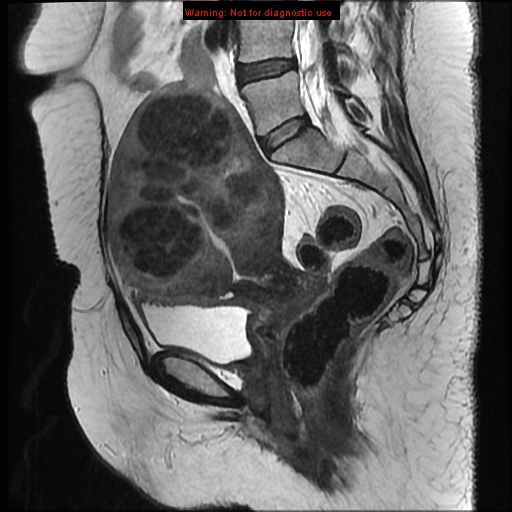

MRI

• US in 2 weeks to assess the uterine size